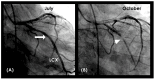

Background: In the study of coronary artery disease, the mechanisms underlying atherosclerosis initiation and progression or regression remain incompletely understood. Our research conceptualized the cardiovascular system as an integrated network of pumps and pipes, advocating for a paradigm shift from static imaging of coronary stenosis to dynamic assessments of coronary flow. Further review of fluid mechanics highlighted the water hammer phenomenon as a compelling analog for processes in coronary arteries. Methods: In this review, the analytical methodology employed a comprehensive, multifaceted approach that incorporated a review of fluid mechanics principles, in vitro acoustic experimentation, frame-by-frame visual angiographic assessments of in vivo coronary flow, and an artificial intelligence (AI) protocol designed to analyze the water hammer phenomenon within an acoustic framework. In the analysis of coronary flow, the angiograms were selected from patients with unstable angina if they had previously undergone one or more coronary angiograms, allowing for a longitudinal comparison of dynamic flow and phenomena. Results: The acoustic investigations pinpointed pockets of contrast concentrations, which might correspond to compression and rarefaction zones. Compression antinodes were correlated to severe stenosis, due to rapid shifts from low-pressure diastolic flow to high-pressure systolic surges, resulting in intimal injury. Rarefaction antinodes were correlated with milder lesions, due to de-escalating transitions from high systolic pressure to lower diastolic pressure. The areas of nodes remained without lesions. Based on the locations of antinodes and nodes, a coronary acoustic action map was constructed, enabling the identification of existing lesions, forecasting the progression of current lesions, and predicting the development of future lesions. Conclusions: The results suggested that intimal injury was likely induced by acoustic retrograde pressure waves from the water hammer phenomenon and developed new lesions at specifically exact locations.